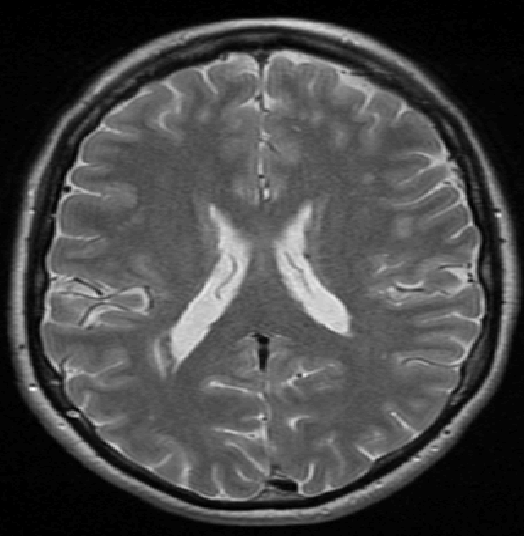

We use images from three different studies (see Fig. 1 for examples of slices):

10 MS patients from the MS Lesion Challenge [11] scanned at the Children’s Hospital of Boston (CHB), scanned with T1, T2 and FLAIR at 0.50.50.5mm resolution.

10 MS patients from the MS Lesion Challenge [11] scanned at the University of North Carolina (UNC), scanned with T1, T2 and FLAIR at 0.50.50.5mm resolution.

- 3.

Here again the differences between study populations influence the class priors. On average, the percentage of voxels that are lesions are 1.6%, 2.6% and 0.2% in CHB, RSS and UNC respectively. The differences between subjects also vary: these are relatively small for CHB and UNC, but very large for RSS. In RSS, the subject with the least lesion voxels has only 0.08%, while the patient with the most lesion voxels has 14.3%.